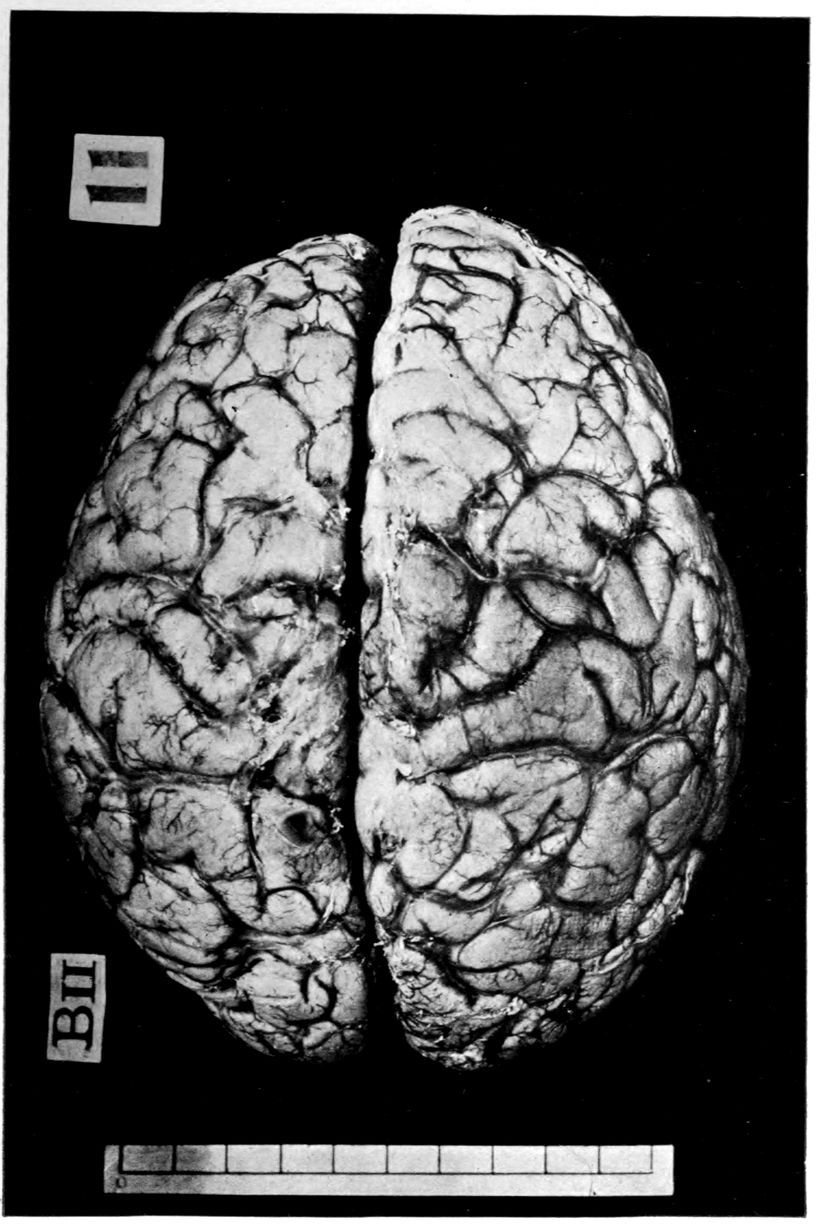

Case 4. James Pierce was an almshouse transfer to the Danvers Hospital in his fiftieth year. He died three years later. The accompanying brain pictures demonstrate so extensive a lesion of the left hemisphere that it is of great interest to determine if possible the genesis and course of his disease. It appears that syphilis had been acquired somewhere about the age of 38 or 40, so that the total duration of the process was between 13 and 15 years. In Pierce’s forty-third or forty-fourth year, he had a shock while walking in the streets of his native city, whereupon he was subsequently transferred to the Danvers Hospital, whose data have been summed up as follows (we are obliged to Dr. Charles T. Ryder for these data):

Head: Calvarium of moderate thickness; diploë present; dura slightly adherent over bregmatic region. Longitudinal sinus contains cruor clot. Dura is somewhat thickened and slightly more opaque than normal. Pacchionian granulations, small but fairly numerous. Pia contains throughout a considerable excess of clear 44serous fluid. The convolutions in general are of good breadth and proportion. There is an atrophic area roughly circular in outline and about 2 cm. in diameter in the posterior part of the right third frontal convolution corresponding to Broca’s area on the opposite hemisphere. The space thus formed is filled with edema held by the pia. On the left side is a similar subpial collection which covers the site of the posterior portions of all of the third frontal convolutions, parts of the lower end of the precentral convolution, and the whole of the first temporal convolution, which have disappeared entirely. The basal vessels show slight changes.

Cerebellum and basal ganglia are grossly normal.

The spinal membranes are negative. The regions of the pyramidal tracts in the cord are firm, project slightly from surface of section, and are china white.

Vascular neurosyphilis—effects of syphilitic thrombosis of Sylvian artery 10 years before death. (Case 4.)